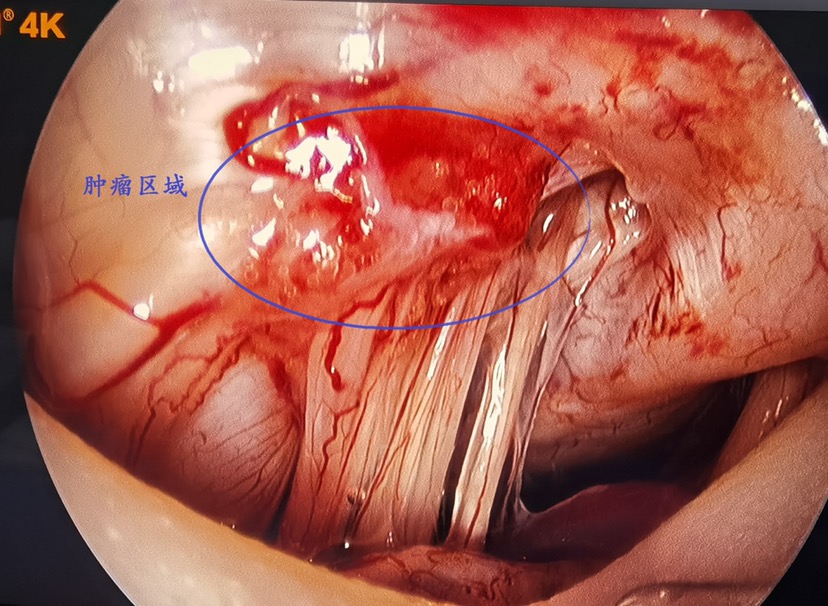

术中显示肿瘤质地较硬,直径约1cm,包绕左侧第Ⅸ、第Ⅹ和第Ⅺ颅神经并与硬脑膜粘连紧密。使用精细磨钻磨除颈静脉孔区部分骨质,充分暴露肿瘤。在电生理监测和德龙4K超高清内镜系统显示下完全切除肿瘤,保留神经,未出现大出血。

我们采取周密的术前计划、超高清内镜显示系统和精密的开颅器械,对颈静脉孔区肿瘤切除时脑膜切开约1元钱硬币大小,能够做到微创开颅、不留死角、全切肿瘤、快速康复。